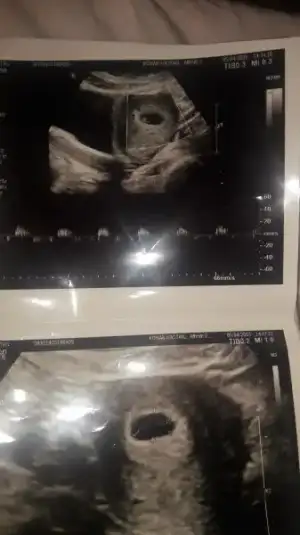

Kimler kimler yazdı?5 haftalıkti keseyi gorduk 6 haftalikti kalp atislarini duyduk ufacik bisey vardı nokta gibi kesenin icinde bu bebek dedi dr bugunde 8 hafta 3 gunluk bebegi gordum canımKızlar Rabbim hepimize sağ salim kucağımıza almayı nasip etsin inşallah, Ben dün 5+5 haftalık olarak gittim doktora kese 18 mm di ama bebeği göremedik haftaya tekrar gel dedi, siz bebeklerinizi karından ultrasonla kaçıncı haftada görebildiniz hatırlıyor musunu?

Hatta bak orda yukardakinde nokta gibi kosede o bebekmis canimKızlar Rabbim hepimize sağ salim kucağımıza almayı nasip etsin inşallah, Ben dün 5+5 haftalık olarak gittim doktora kese 18 mm di ama bebeği göremedik haftaya tekrar gel dedi, siz bebeklerinizi karından ultrasonla kaçıncı haftada görebildiniz hatırlıyor musunu?

O zaman benimki normal yani, inşallah haftaya güzel haberler alırım Rabbimin izniyle..Hatta bak orda yukardakinde nokta gibi kosede o bebekmis canim

Karından 7 haftalık gördükKızlar Rabbim hepimize sağ salim kucağımıza almayı nasip etsin inşallah, Ben dün 5+5 haftalık olarak gittim doktora kese 18 mm di ama bebeği göremedik haftaya tekrar gel dedi, siz bebeklerinizi karından ultrasonla kaçıncı haftada görebildiniz hatırlıyor musunu?

Karından 7 haftalık gördük

Bu da dünden benim bebeemm